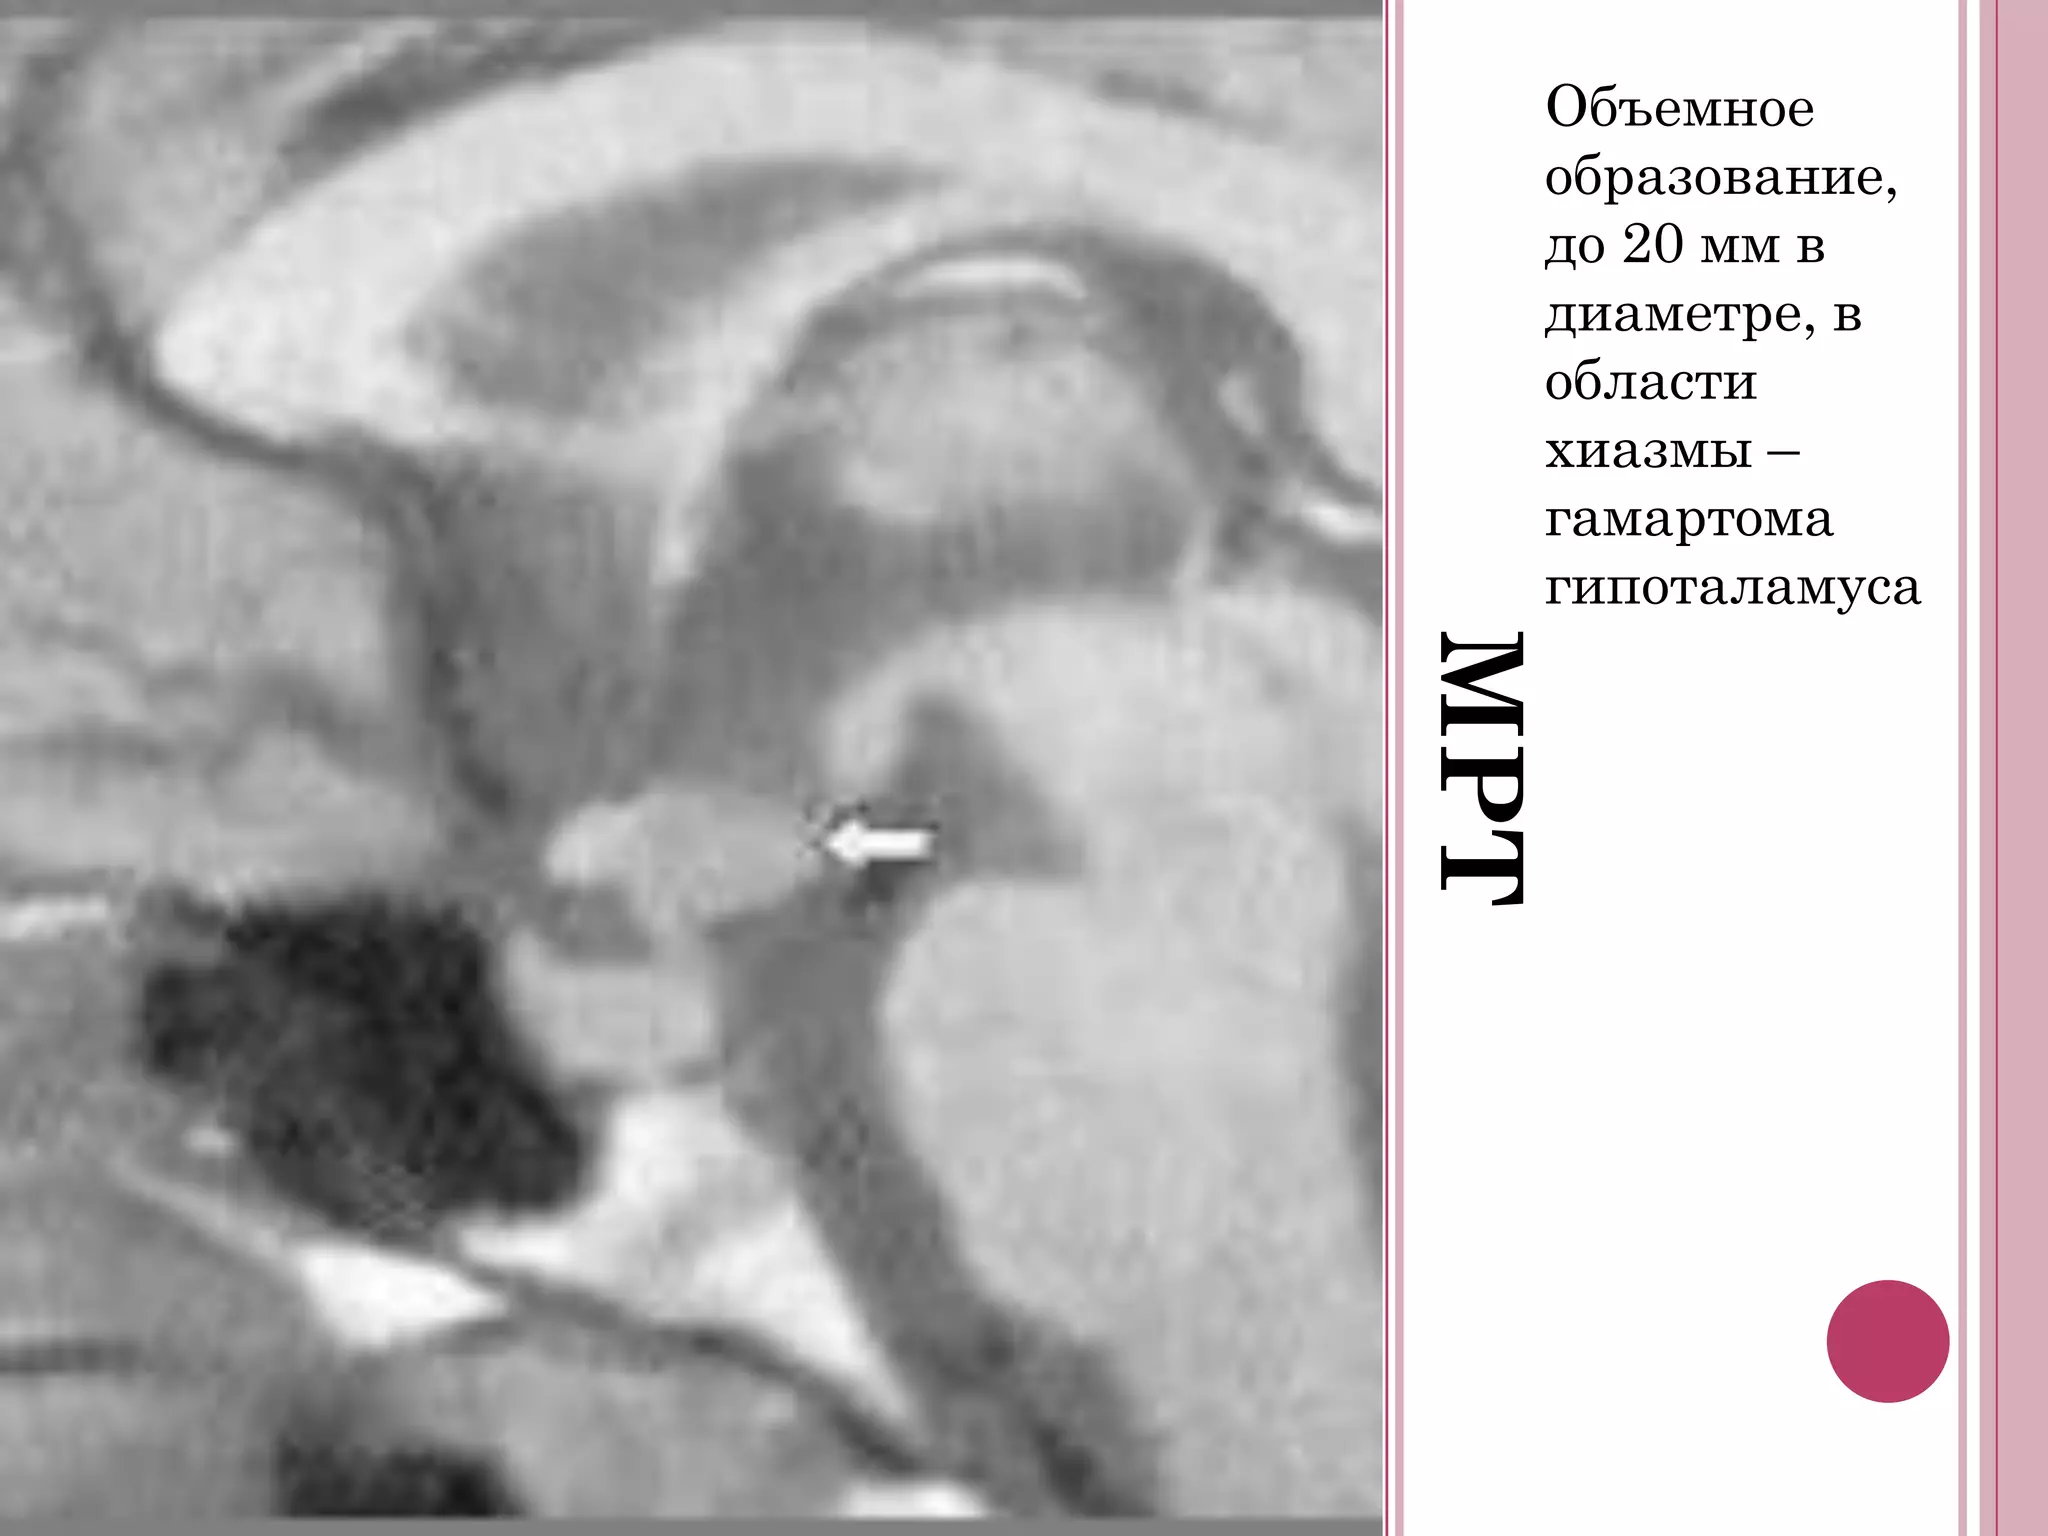

Объемное

образование,

до 20 мм в

диаметре, в

области

хиазмы –

гамартома

гипоталамуса

МРТ

Объемное образование, до 20 мм в диаметре, в области хиазмы – гамартома гипоталамуса МРТ